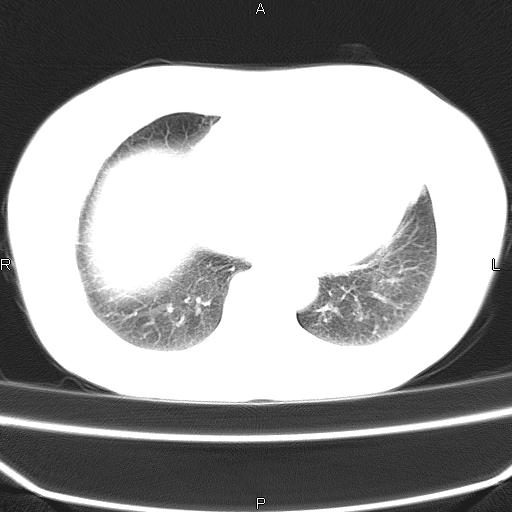

患者,女,66岁。健康体检胸部透视发现右上肺片状阴影。既往无不适,患者自诉三个月前曾有低热病史体温37.5左右一周。用药后缓解。至今无其它不适。请老师们指导指导。

考虑:右肺上叶周围型肺癌(分叶状肿块+砂粒状钙化+胸膜尾征)。

病灶见明显分叶、大小较大(大于3cm?),老年人,多考虑:肺癌,建议穿刺活检。

周围性肺癌可能性大,建议增强

右肺上叶周围型肺癌可能性大。

考虑:右肺上叶周围型肺癌